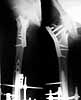

This 19-year-old girl was on long-term follow up after a major trauma (picture-01).

At the age of 9 years she was involved in a road traffic accident in which she suffered:

1) Closed fracture left femur midshaft,

2) Compound fracture right upper femur,

3) Compound fracture right side pelvis,

4) Degloving right lower thigh and leg etc.

At that time she was treated with care of wounds, external fixation of right femur, plating of left femur, skin grafting of right leg etc.